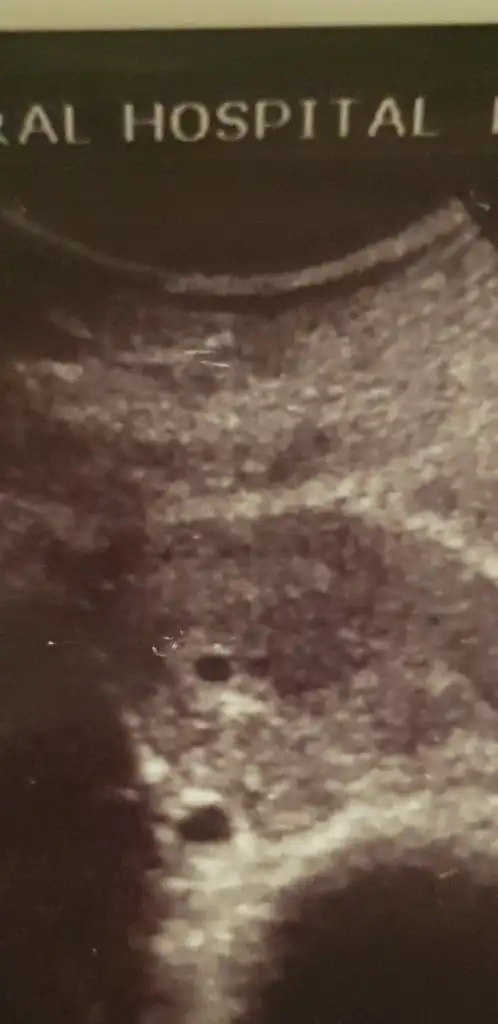

Bu yüklediğim görüntü kardeşimin eşine ait. Bizim gelin hamiş. Son adeti 20 eylül. İkinci çocuk olucak kısmetse. Şuan 14 yaşında oğlu var. Baya ara vermişti 14 yıl sonra bebiş istediler. Yaşı şuan 39...

25 ekimde hcg 2 000 çıktı. P tesi yani 28 inde doktora gitti. Kesenin boyutunu ölçememiş doktor. Haliyle haftasını da hesaplayamamış Şuan kesenin ölçüsü elimizde yok. Resimde üstteki siyahlık kesekiz. Altta ki de 2.54 cm çıkan kist. Keseden büyük kist varmış. Biz bu işin işinden çıkamadık lütfen fikir söyleyin

Bu arada pregestronu 11 çıkmış. Hap vermiş. Birde ferritin çok çok düşük 1.5 çıkmış